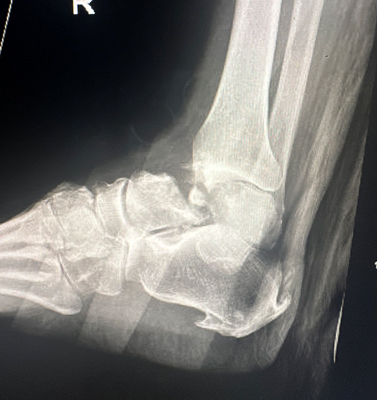

TOTAL ANKLE REPLACEMENT :: ORIF CALCANEUS :: ORIF ANKLE FRACTURE DISLOCATION :: COMPLEX BUNION AND LESSER TOE CORRECTION :: TALUS FRACTURE -1 :: TALUS FRACTURE -2 :: LISFRANC REPAIR :: COMPLEX TRIPLE ARTHRODESIS 1 :: COMPLEX TRIPLE ARTHRODESIS 2 :: MINIMALLY INVASIVE BUNION REPAIR 1 :: MINIMALLY INVASIVE BUNION REPAIR 2 :: ARTHROSCOPIC CARTILAGE REPAIR :: TENEX SPUR DEBRIDEMENT :: Haglunds Debridement and Achilles Repair